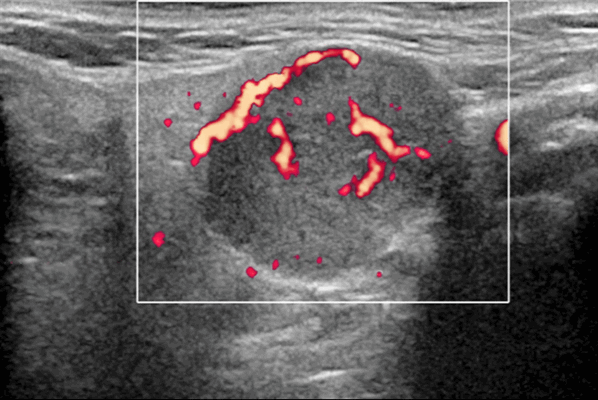

- Цветной допплер: периферические сосуды, в основном венозные.

Цветной допплер. Периферические сосуды, в основном венозные, часто редко расположены. Спектральный допплер: низкое внутриузловое сопротивление сосудов [резистивный индекс (RI) Результаты MРТ